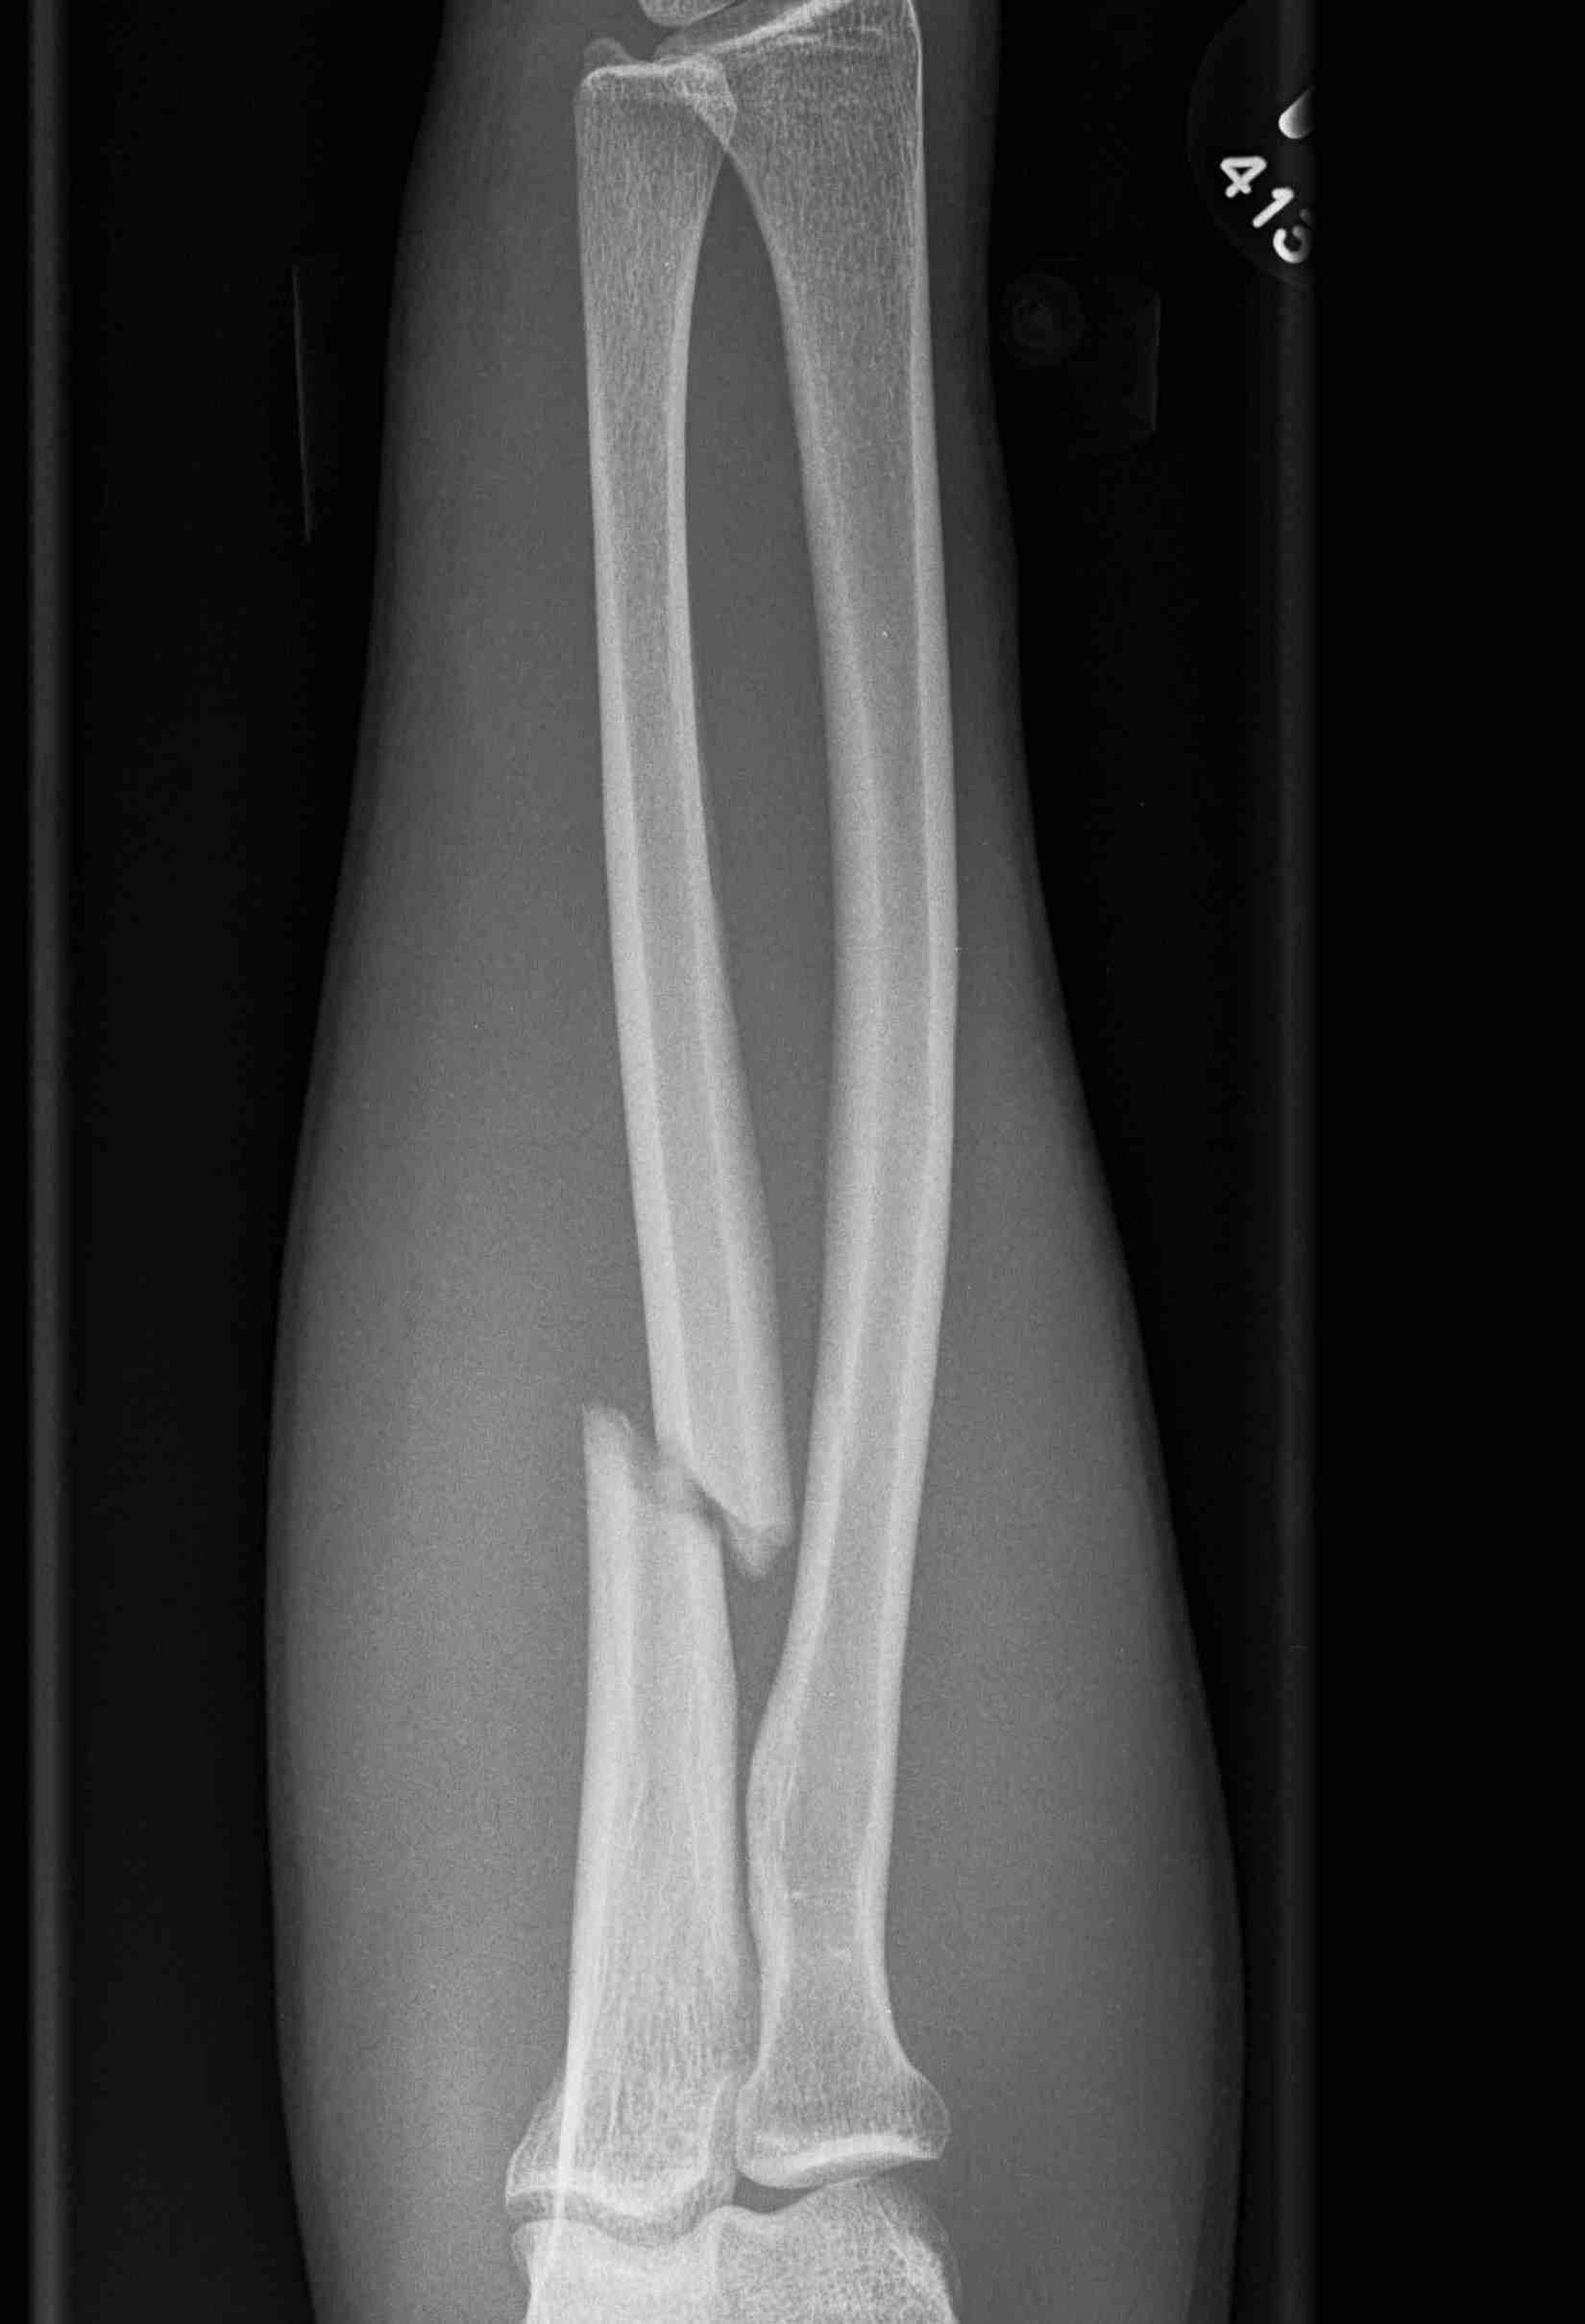

Acute fractures

- > 50% displacement

- > 10 degrees angulation

- midshaft ulna fractures - higher risk of nonunion

Ulna nonunion after plating